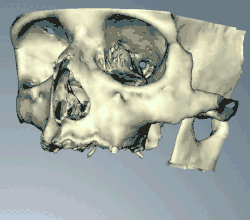

When a more exacting plan is needed beyond clinical judgment, the dentist will make an acrylic guide (called a stent) prior to surgery which guides optimal positioning of the implant. Increasingly, dentists opt to get a CT scan of the jaws and any existing dentures, then plan the surgery on CAD/CAM software. The stent can then be made using stereolithography following computerized planning of a case from the CT scan. The use of CT scanning in complex cases also helps the surgeon identify and avoid vital structures such as the inferior alveolar nerve and the sinus.[49][50]: 1199